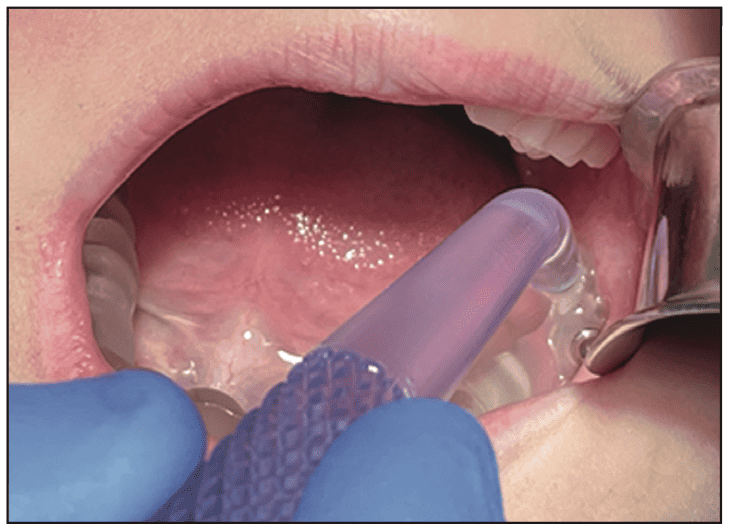

Based on animal trials, the 3TBA procedure in humans will be as fast and simple. Designed for children ages 6 to 12, fully guided 3TBA involves accurate positioning of a 3TBA micro-ablation handpiece using a 3TBA guide. Positioning of the 3TBA micro-ablation handpiece tip is predetermined with 0.1 mm planning resolution. The full-arch 3TBA guide is first seated onto patients’ teeth. The disposable 3TBA micro-ablation handpiece is then fully seated into the 3TBA guide, as shown in Figure 2. If an osteotomy is required, a 2-mm bone drill can be used to enable complete insertion of the 3TBA handpiece.

Figure 2. The mock 3TBA handpiece inserted into a full-arch 3TBA guide as part of a pilot human trial.